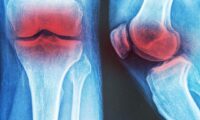

4. 関節の損傷を遅らせる

関節炎などの関節関連疾患は、日常生活に影響を与え、痛みの増加や運動の制限を引き起こす可能性があります。しかし、定期的なウォーキングは、その進行を遅らせ、関節機能を改善するのに役立ちます。

2022年に実施された観察研究では、50歳以上の個人を追跡したデータを使用し、ウォーキングが変形性関節症の症状を緩和し、進行を遅らせる可能性があることが示唆されました。ウォーキングをする人は、しない人に比べて、新たな頻繁な膝の痛みを発症するリスクが40%低く、関節の狭窄(変形性関節症の進行のサイン)のリスクが20%減少しました。これらの発見は、ウォーキングがこの状態の管理に推奨される一部であることを裏付けています。